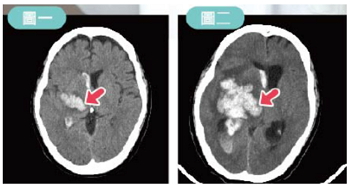

一名52歲男士,日前突然出現左側肢體無力至急診,電腦斷層掃描發現右側大腦半球基底核出血(圖一),由於血腫體積不大且意識尚未陷入昏迷,所以醫生決定暫時先入住神經外科加護病房密切觀察。

翌日淩晨意識變化,出現「腦脫疝」症狀,電腦斷層掃描追蹤出現血腫擴大(圖二),手術處理後狀況改善挽回生命。這樣的個案在外科加護房並不少見。